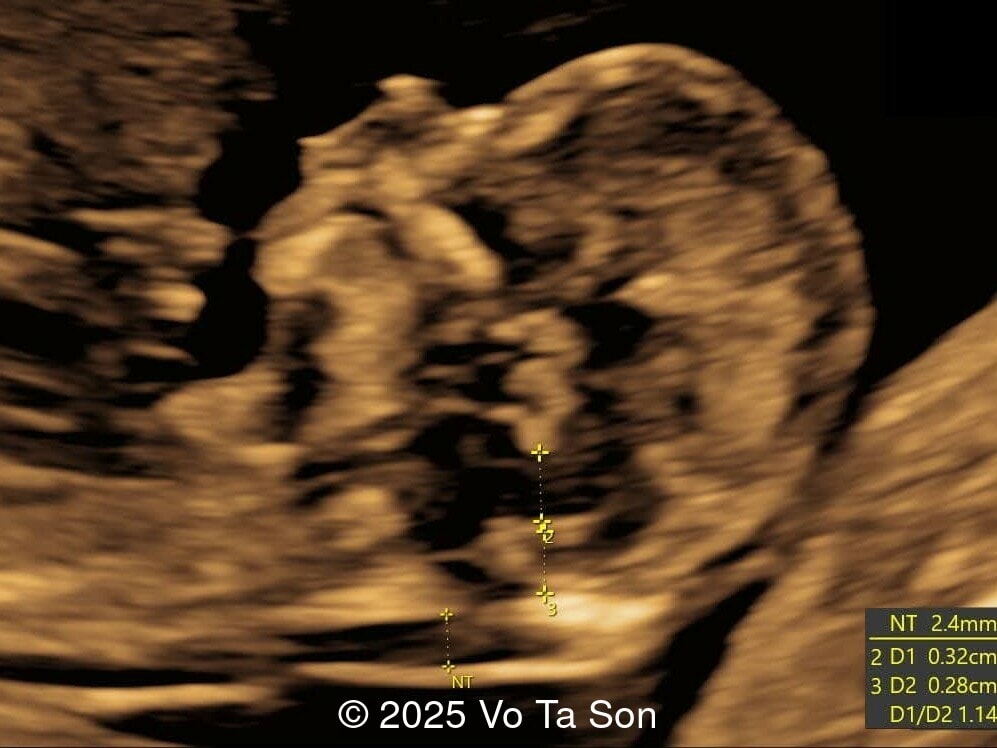

A woman underwent routine prenatal screening at 13 weeks. The non-invasive prenatal test (NIPT) showed low risk for common aneuploidies including trisomy 21, 18, and 13. However, first-trimester anomaly scan revealed multiple fetal anomalies.

We present a case of Triploidy with a 69,XXY chromosomal complement and open spina bifida in the first trimester.

Our imaging revealed the following significant fetal abnormalities:

• Thin nasal bone

• Open spina bifida in the sacral region with dry brain sign, crash sign, BS/BSOB >1, and a lesion at the sacral coccygeal spine. The spinal lesion observed in the sacral region is characterized by a posterior vertebral arch defect and a protruding meningeal sac.